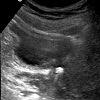

УЗИ уретры

УЗИ мочеиспускательного канала. Ультразвуковое исследование мочеиспускательного канала, проводимое только у мужчин. Техника используется для визуализации мочеиспускательного канала и позволяет оценить его структуру, состояние стенок и ширину просвета. Исследование используется для диагностики воспаления и склеротических изменений в мочеиспускательном канале и показывает аномальные образования уретры у мужчин. Процедура неинвазивна и проводится амбулаторно. Если требуется предварительная подготовка зоны исследования, в мочеиспускательный канал вводится специальная жидкость либо через катетер, либо непосредственно через шприц. УЗИ мочеиспускательного канала может быть выполнено в сочетании с УЗИ мочевого пузыря, мошонки и полового члена.